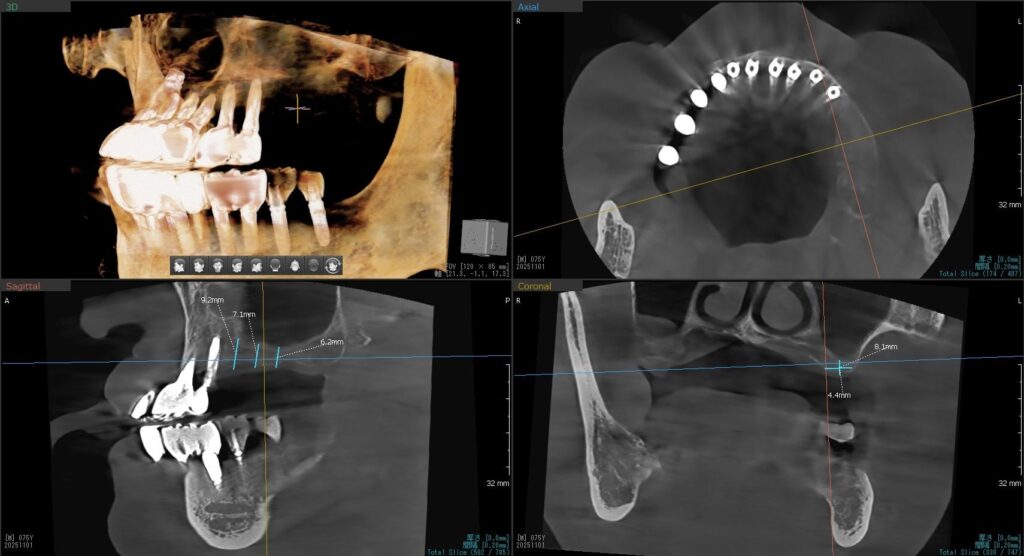

今回の患者様はインプラント植立を希望され、左上5番目・6番目・7番目の3本の植立が決まりました。

ドリルの先端を細い物から徐々に大きい物に変えながら、植立するインプラント体のネジの部分を除いた胴の部分の太さに合わせた大きさの穴を開けていきます。

開けた穴に、専用道具を使ってネジを締めるように長さ2センチ程のインプラントを骨に埋め込んでいきます。